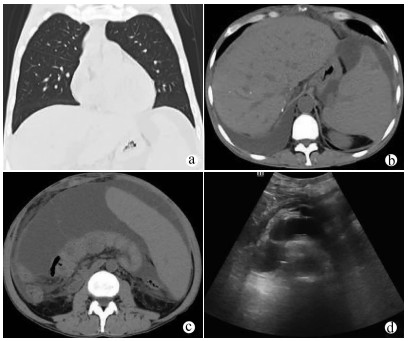

Clinical features of Dubin-Johnson syndrome: An analysis of 10 cases

Abstract(1124) HTML (343) PDF (2389KB)(100)

Abstract: